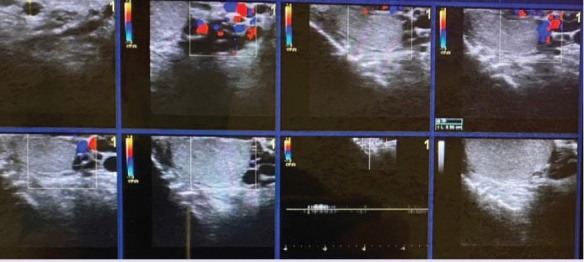

Objective: Only few cases of intratesticular varicocele (ITV) have been reported in the literature, mostly as single cases or a case series. In this study, we aimed to describe the topographic distribution of ITVs in the testicular parenchyma and the correlation between ITV accompanying extratesticular varicocele (ETV) and age.

Methods: Approximately 10,537 patients with scrotal pain and swelling who visited our hospital between August 2014 and May 2020 and underwent scrotal colour Doppler ultrasonography were included in this study. Of these patients, 2285 had ETV, and the remaining patients (n=8252) had other testicular pathologies such as acute-chronic torsion, testicular mass, orchitis, significant testicular atrophy, or isolated extratesticular varicocele, and were thus excluded from the study. Among the 2285 patients, only 20 had ITV.

Results: Of the 20 patients with ITV, 2 had isolated ITV, and the remaining had ITV accompanying ETV, of whom only one had a right ETV. One patient had left testicular atrophy accompanying an isolated ITV. Among the ITV cases, subcapsular ITV was the most common (n=13), followed by central ITV (n=4) and subcapsular and hilar ITV (n=3). The patients' ages ranged from 18 to 30 years.